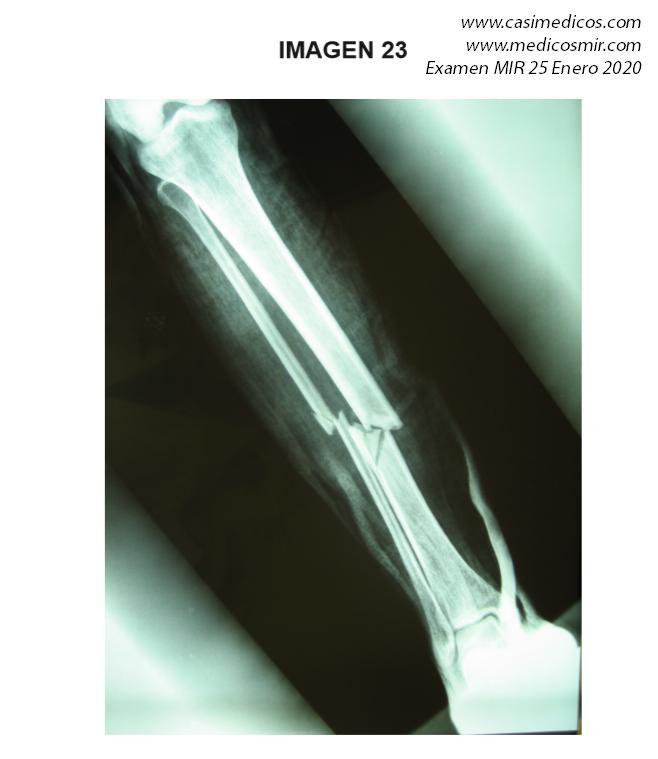

Pregunta vinculada a la imagen nº 23

Un paciente presenta una fractura cerrada cuya radiografía en proyección ántero-posterior puede revisar en la imagen adjunta. ¿Cuál de las siguientes opciones de tratamiento le parece correcta?:

- Clavo intramedular acerrojado proximal y distal

- Ortesis de tipo PTB (patellar tendón bearing) y deambulación desde el momento inicial.

- Fijador externo circular y deambulación precoz.

-

Reducción abierta y placa y tornillos bloqueados.

Respuesta correcta: 1

Comentario:

En una factura diafisaria la tendencia es el enclavado endomedular bloqueado a proximal y distal.

La ortesis la plantearíamos en una fractura sin desplazamiento y en casos seleccionados para fracturas muy benignas dado que el enclavado endomedular permitiría movilización y carga precoz.

El fijador externo se utilizaría en una fractura abierta o una fractura compleja que precisara dos tiempos en su manejo (un pilón tibial, por ejemplo).

Realmente la respuesta 4 también se podría plantear pero con el clavo se puede iniciar antes la carga.

Opción 1: Actualmente se acepta el enclavado intramedular como el tratamiento de elección para el tratamiento de las fracturas diafisarias de tibia desplazadas o inestables. Nota personal: el fragmento en cuña denota cierta inestabilidad de la fractura

Sobre la opción 2: Requiere la colocación de un yeso desde la región proximal del muslo, con un moldeado cuidadoso en la región supracondílea que evite el desplazamiento distal del yeso, e incluye el tobillo en posición neutra (yeso cruropédico). Este yeso será sustituido por un yeso de apoyo en el tendón rotuliano (yeso funcional PTB) o por una ortesis funcional cuando disminuya el edema y el paciente sea capaz de deambular con apoyo, lo que en general ocurrirá a partir de las 3-4 semanas. quedando por tanto descartada esta opción, al no permitir carga desde el momento inicial.

Sobre la opción 3: No es considerado el tratamiento de elección en la actualidad para el tratamiento de las fracturas diafisarias de tibia. Su indicación actual queda limitada como tratamiento inicial de elección en fracturas diafisarias abiertas o cerradas secundarias a traumatismos de alta energía

Sobre la opción 4: No es considerado el tratamiento de elección en la actualidad para el tratamiento de fracturas diafisarias de tibia. Su indicación actual queda limitada a aquellas fracturas diafisarias de tibia con extensión metafisaria o articular.